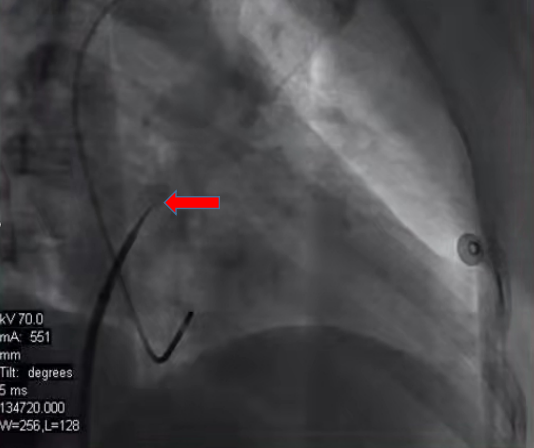

传统的房颤射频消融术从股静脉穿刺导管入路到房间隔穿刺、射频治疗,都依赖于X射线透视下进行操作,透视时间长、射线量大,并且定位是通过二维的形式展现。但是穿刺位点解剖位置及结构并不能够在X线影像完美呈现。

红色箭头所示的穿刺点无法准确判定是否为最佳穿刺点,安全性、可靠性较差。穿送过去之后,还需要造影证实,且需要多体位左心房—肺静脉造影,判断肺静脉解剖形态。